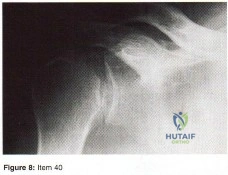

- Tear of the rotator cuff

- Injury to the brachial plexus

- Fracture of the upper thoracic rib

- Fracture of the proximal humerus